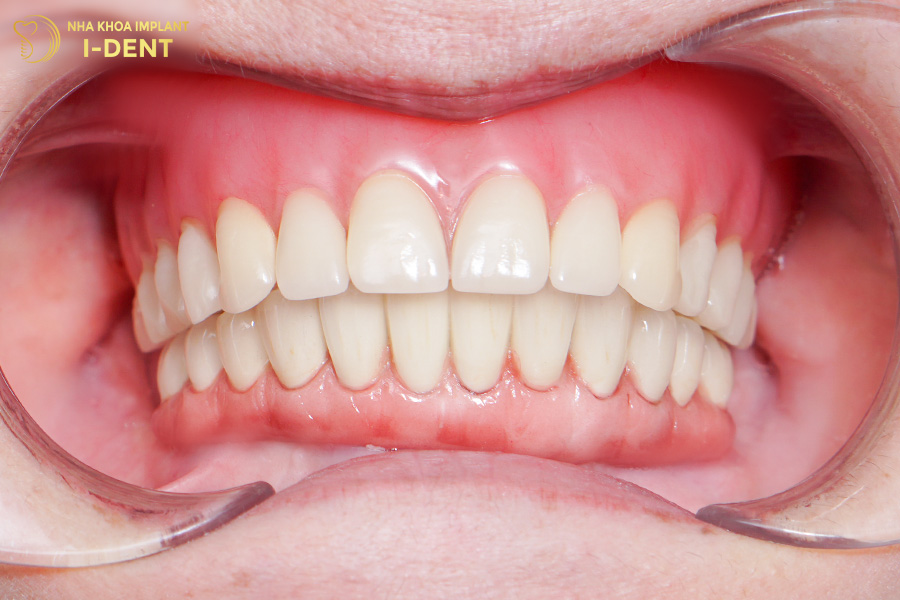

Sau khi có răng mới, chú Hải không còn phải chịu đựng tình trạng đau nhức răng và khó ăn nhai, sức khỏe của Chú cũng được cải thiện hơn rất nhiều.

Tình trạng răng sau khi cấy ghép implant All on 4 cho 2 hàm của chú Nguyễn Hải

Kết thúc thời gian theo dõi và điều trị, bệnh nhân đã có thể ăn uống ngon miệng hơn trước và cũng nhờ đó mà sức khỏe cũng có bước cải tiến rõ rệt.

Hình ảnh răng chú Sự sau khi cấy ghép Implant All on 4 cho hàm trên